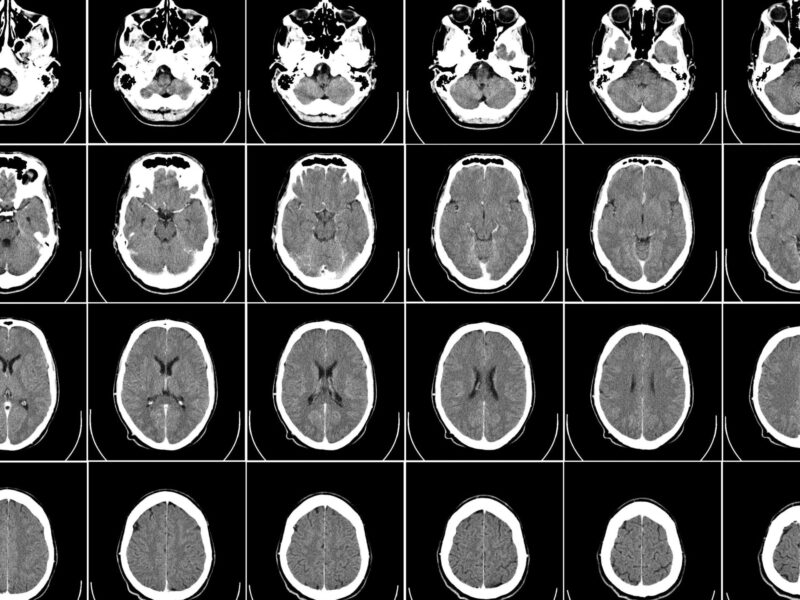

Un estudio con participación del Hospital Universitari Institut Pere Mata, el IRB CatSud y la URV identifica alteraciones en el comportamiento genético que podrían contribuir a mejorar su predicción clínica en el futuro